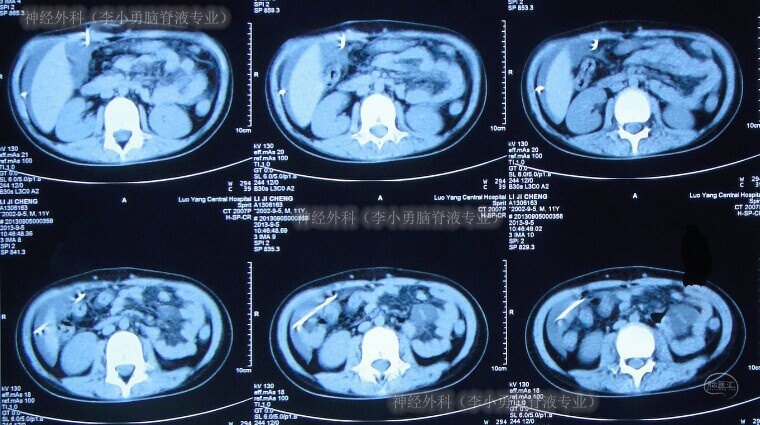

第1次分流管调整术1年5个月后即2013年8月19日(患儿11岁时),再次出现呕吐、腹部膨隆;于是当天就诊(第3次)于河南省洛阳市某医院,查CT显示第四脑室及侧脑室均显著再扩大(图-5);且腹部CT再示分流管周围出现包裹性积液(片子遗失)。给予经分流管泵抽吸脑脊液进行细菌培养,并给予抗炎、脱水等处理。

图-5:2013年8月19日头颅CT

术后第16日即2012年9月5日,症状好转出院;出院时查腹部CT显示右侧腹腔内可见分流管影,其周围无异常(图-6)。

图-6:2013年9月5日腹部CT

第2次分流管腹腔端调整术2个半月后即2013年11月4日,再次出现呕吐、腹部膨隆等表现,当日第4次就诊于河南省洛阳市某医院,复查腹部CT显示右侧腹腔内分流管周围出现大量的包裹性积液(图-7)。

图-7:2013年11月4日腹部CT